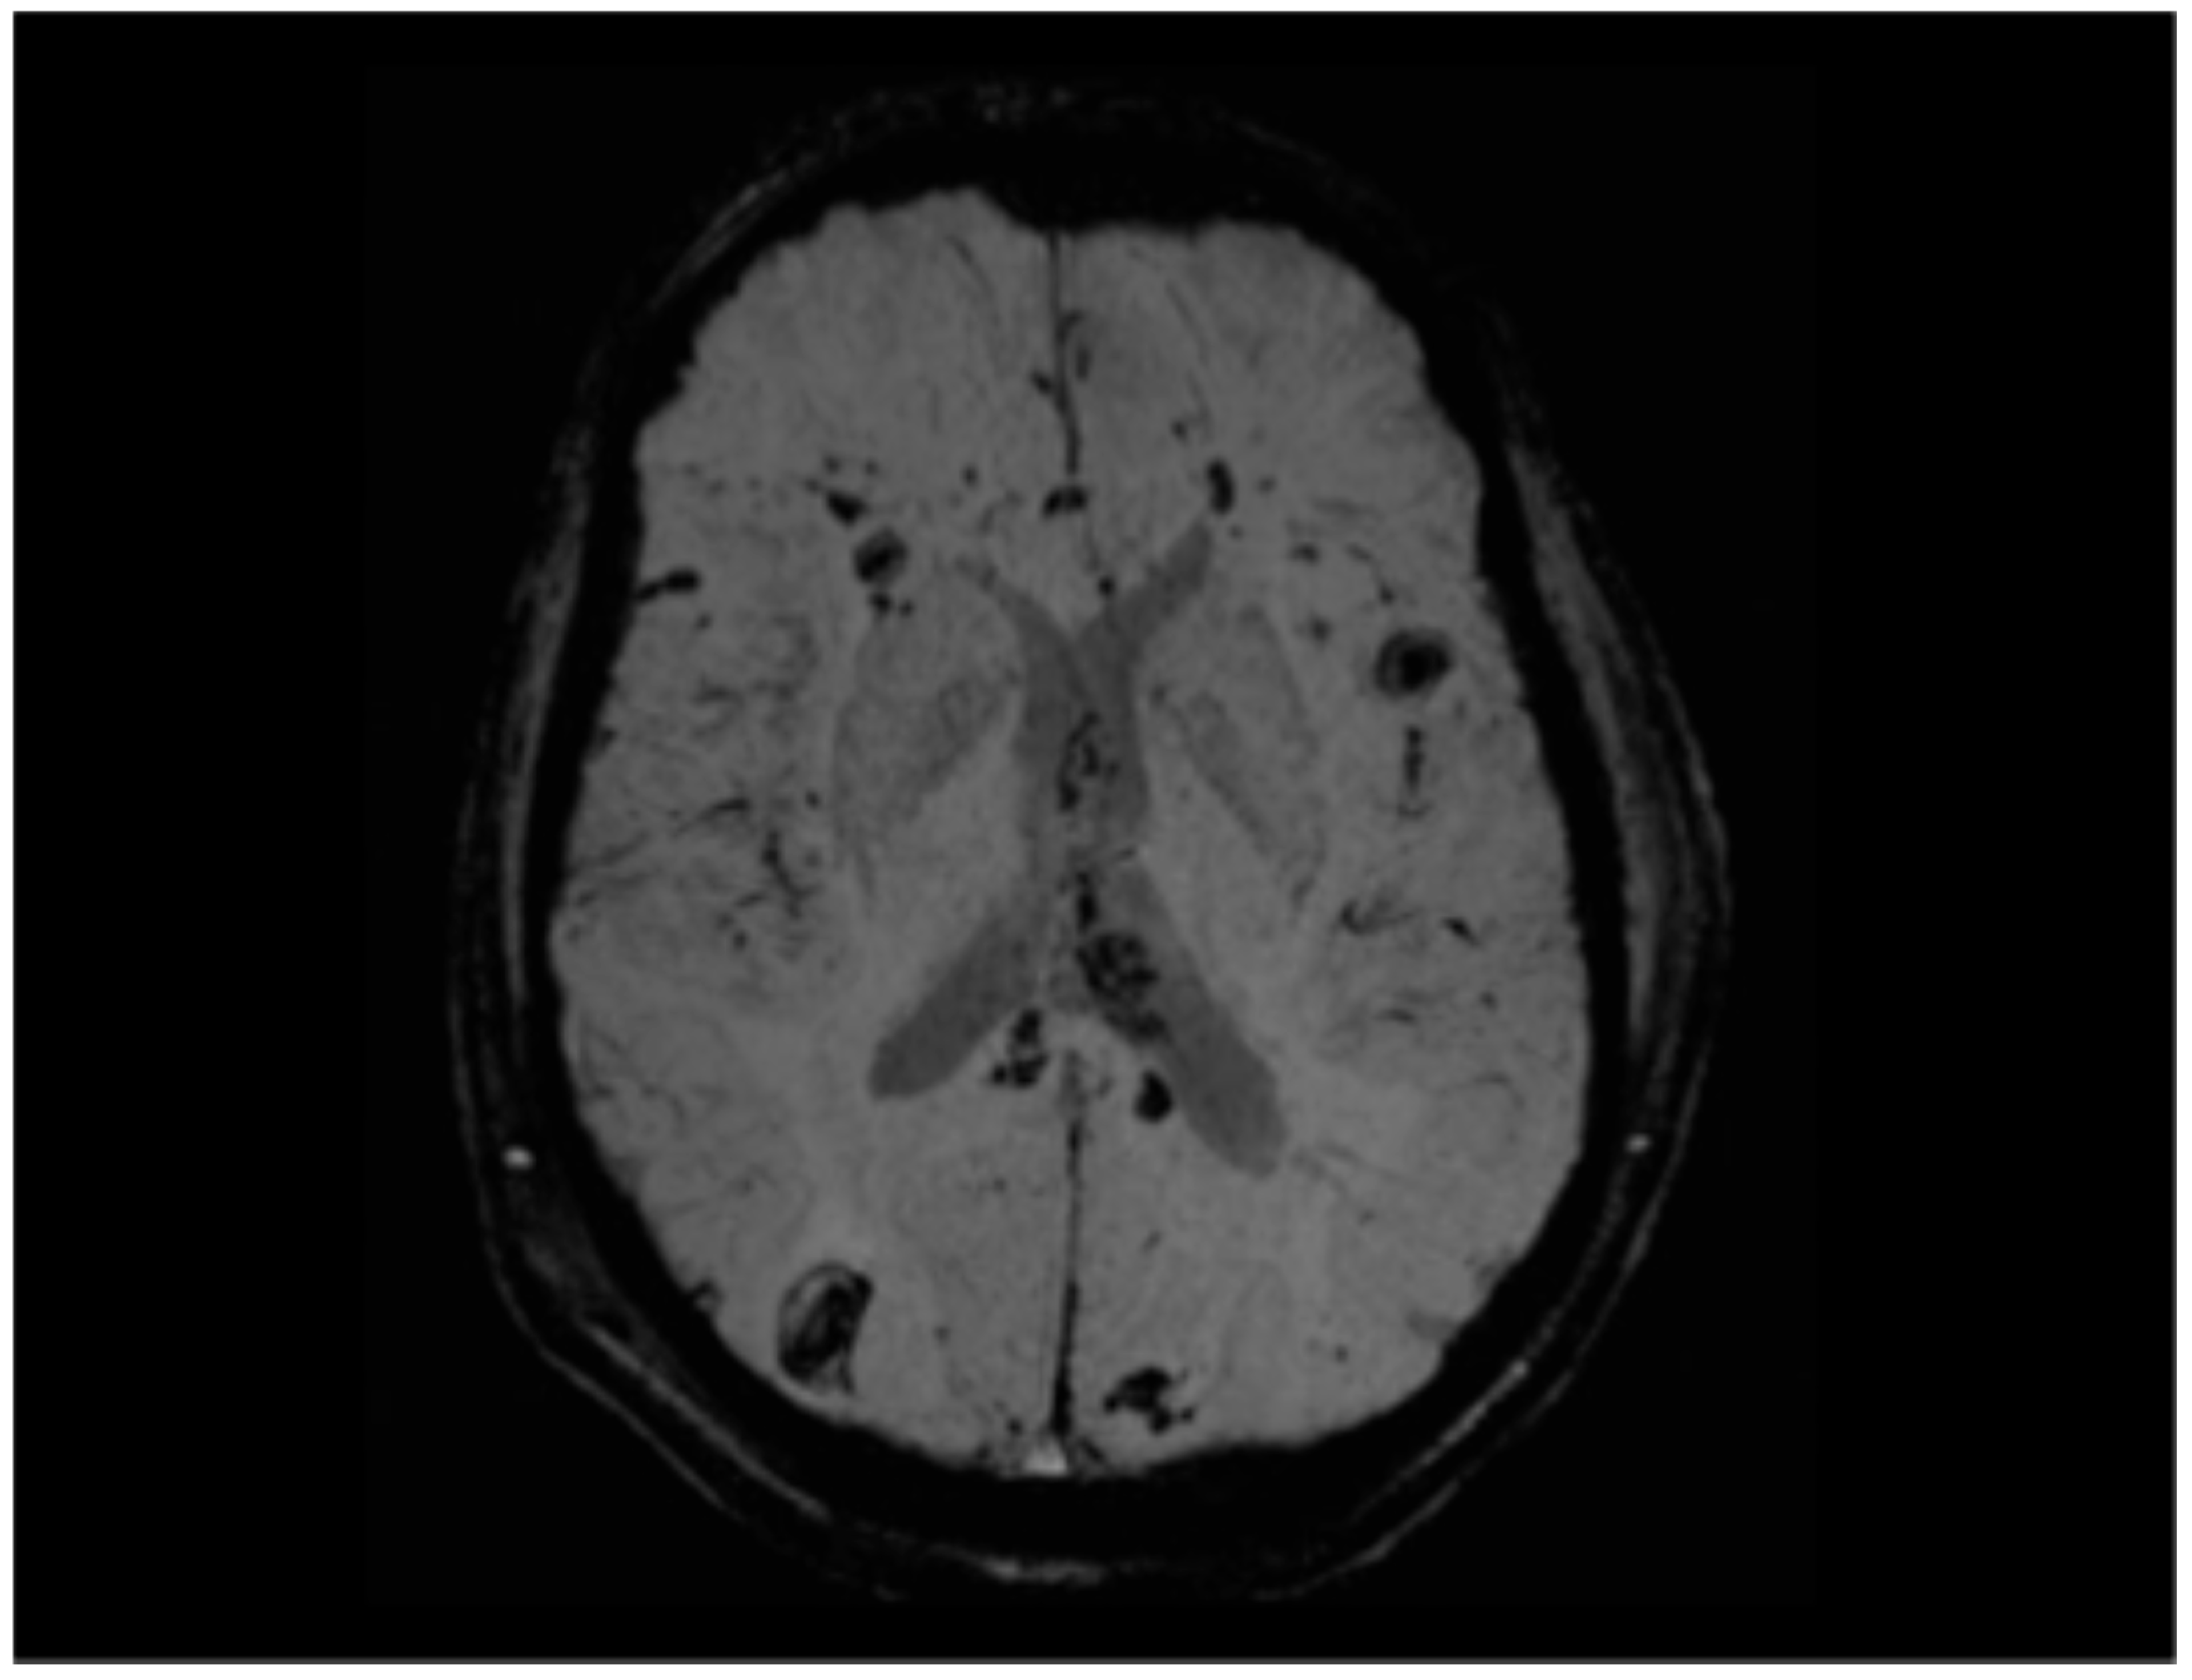

5.3.1. Radiological Findings in Adult DAI

- Ravikanth, R.; Majumdar, P. Prognostic significance of magnetic resonance imaging in detecting diffuse axonal injuries: Analysis of outcomes and review of literature. Neurol. India 2022, 70, 2371–2377. [Google Scholar] [CrossRef] [PubMed]

- Abu Hamdeh, S.; Marklund, N.; Lannsjö, M.; Howells, T.; Raininko, R.; Wikström, J.; Enblad, P. Extended anatomical grading in diffuse axonal injury using MRI: Hemorrhagic lesions in the substantia nigra and mesencephalic tegmentum indicate poor long-term outcome. J. Neurotrauma 2017, 34, 341–352. [Google Scholar] [CrossRef]

- Moen, K.G.; Flusund, A.M.H.; Moe, H.K.; Andelic, N.; Skandsen, T.; Håberg, A.; Kvistad, K.A.; Olsen, Ø.; Saksvoll, E.H.; Abel-Grüner, S.; et al. The prognostic importance of traumatic axonal injury on early MRI: The Trondheim TAI-MRI grading and quantitative models. Eur. Radiol. 2024, 34, 8015–8029. [Google Scholar] [CrossRef]